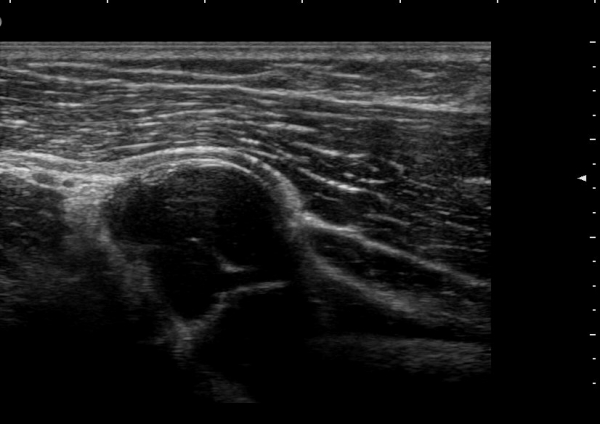

Á¾´Ü¸é°Ë»ç¿¡¼­ Àú¿¡ÄÚ ³¶Á¾ÀÇ Ç¥Ãþ¿¡¼­ Èİñ°£½Å°æºÐÁö°¡ ÀüÀ§µÇ¾î °üÂûµÈ´Ù(±×¸² 4, 5, 6).